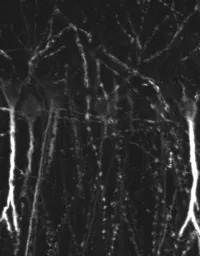

IHC-P analysis of rat hippocampus tissue using GTX79241 Somatostatin receptor 4 antibody.

Green : Primary antibody

Red : Somatostatin-containing terminals

IHC-P analysis of hippocampus tissue using GTX79241 Somatostatin receptor 4 antibody.